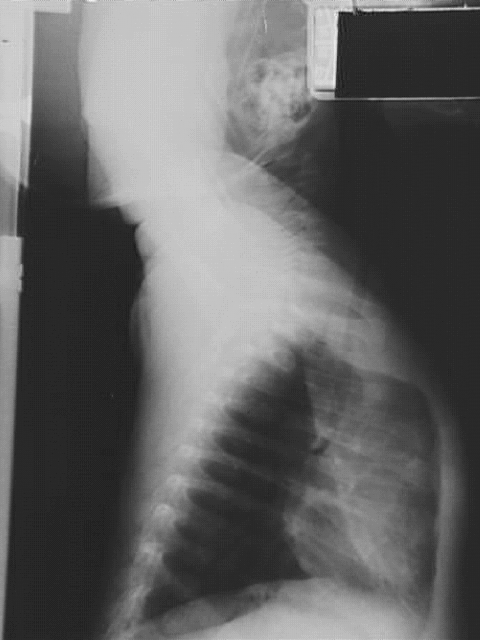

Thorax- Chest Lateral